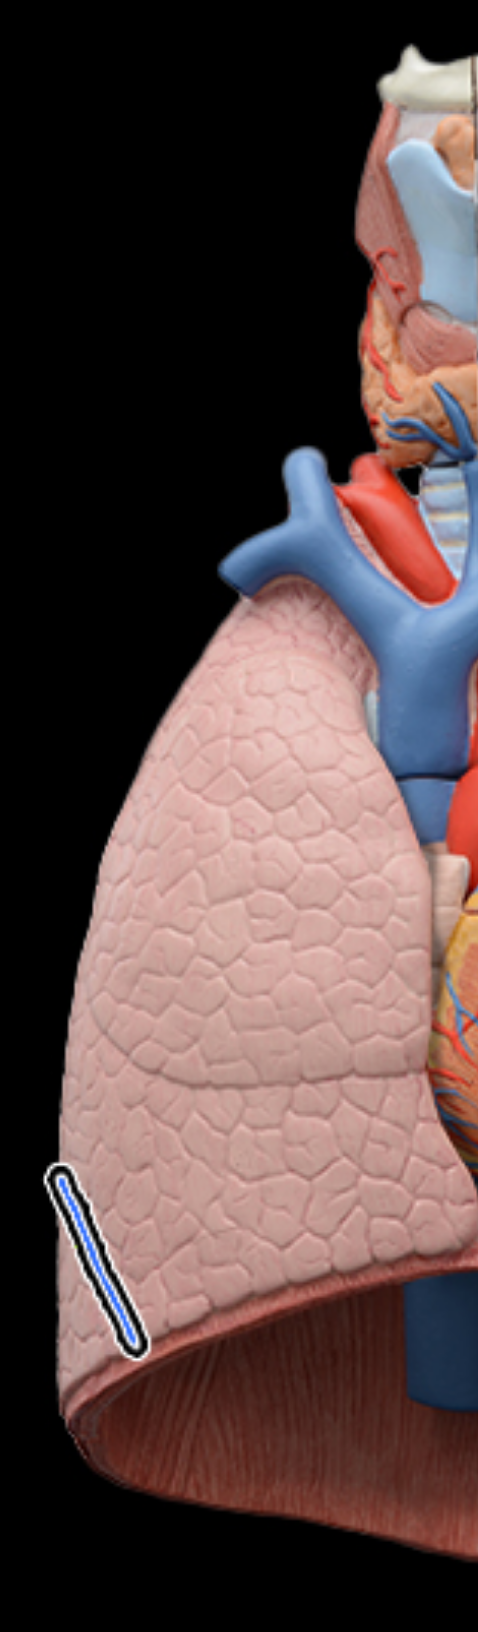

Superior, lobe of right lung

middle lobe of right lung

inferior lobe of right lung

Horizontal fissures of right lung

oblique fissures of right lung

Superior lobe of left lung

inferior lobe of left lung

oblique fissure of left lung

cardiac notch